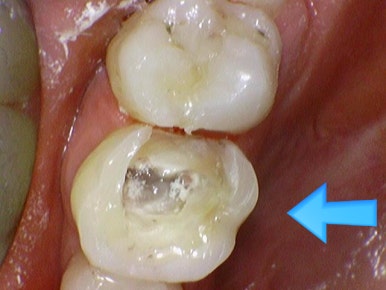

신경치료하고 크라운 안 한 치아->파절

위의 케이스도 비슷합니다.

신경치료를 외국에서 했는데 외국에서는 크라운 비용이 더 비싸다보니 방치해서

크라운으로 치아를 감싸지 못해 치아가 다 부러지고 저렇게 뿌리부분만 남아

크라운조차 할 수 없는 경우가 많습니다.